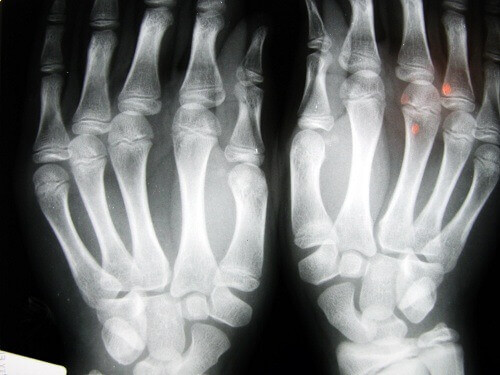

Många undrar om knäckning av knogar eller leder kan resultera i artrit, och som vi sagt ovan finns det flera studier kring detta. Sanningen är att om det är en daglig vana under loppet av många år kan brosket skadas – rent teoretiskt.

En av de mest kända studierna kring detta område utfördes av Dr. Donald Unger, som i mer än 60 år knäckte knogarna på sina fingrar på sin vänstra hand två gånger om dagen samtidigt som han lät sin högra hand vara. Varje år undersökte han sina händer, men hittade aldrig spår av någon degenerativ sjukdom i handen vars knogar han knäckte.

En annan studie följde 30 äldre personer på ett vårdhem i Los Angeles. De som hade knäckt sina knogar under hela sina liv hade inte artros. En tredje studie, den här gången med vuxna på 45 år i Detroit, upptäckte att de största problemen var förlust av styrka i handgreppet samt att över 80% av de studerade drabbades av svullnad i sina händer.